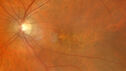

Chorioretinal Folds Radiating from Contracted Fibrovascular Pigment Epithelial Detachment

radiatingfoldsamd_sara07.jpg